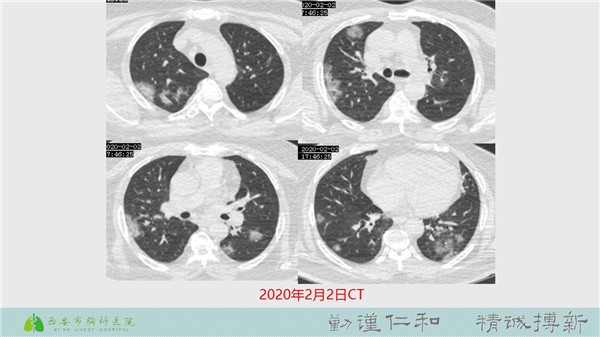

【病例分享】新型冠狀病毒肺炎4例(西安市胸科醫(yī)院)

發(fā)布時間:2020-02-10  瀏覽量:1716